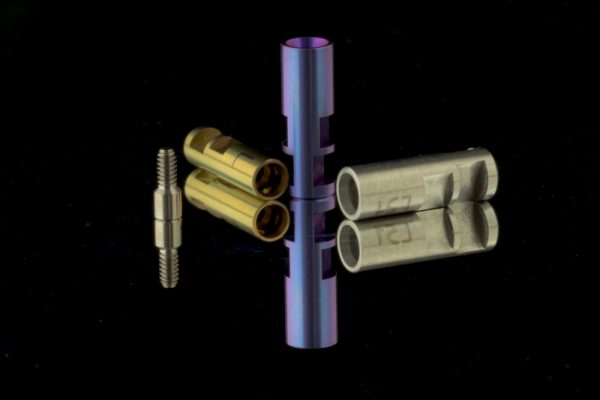

Implantat-Prothetik

Implantate sind die Alternative zu herkömmlichen Versorgungen mit Brücken und Prothesen. Diese können Einzelzahnversorgungen, fest verankerte oder herausnehmbare Brücken tragen oder herausnehmbare Prothesen stabilisieren. Aber auch der Verlust von mehreren oder sogar allen Zähnen lässt sich sehr häufig mit Implantat-Lösungen kompensieren. Im Bereich der Implantat-Prothetik gibt es sehr viele unterschiedliche Lösungsmöglichkeiten und natürlich auch ein großes Spektrum an Materialien. Nähere Informationen zu diesen ästhetischen und komfortablen Zahnersatz-Lösungen geben wir Ihnen gerne – nehmen Sie Kontakt mit uns auf.